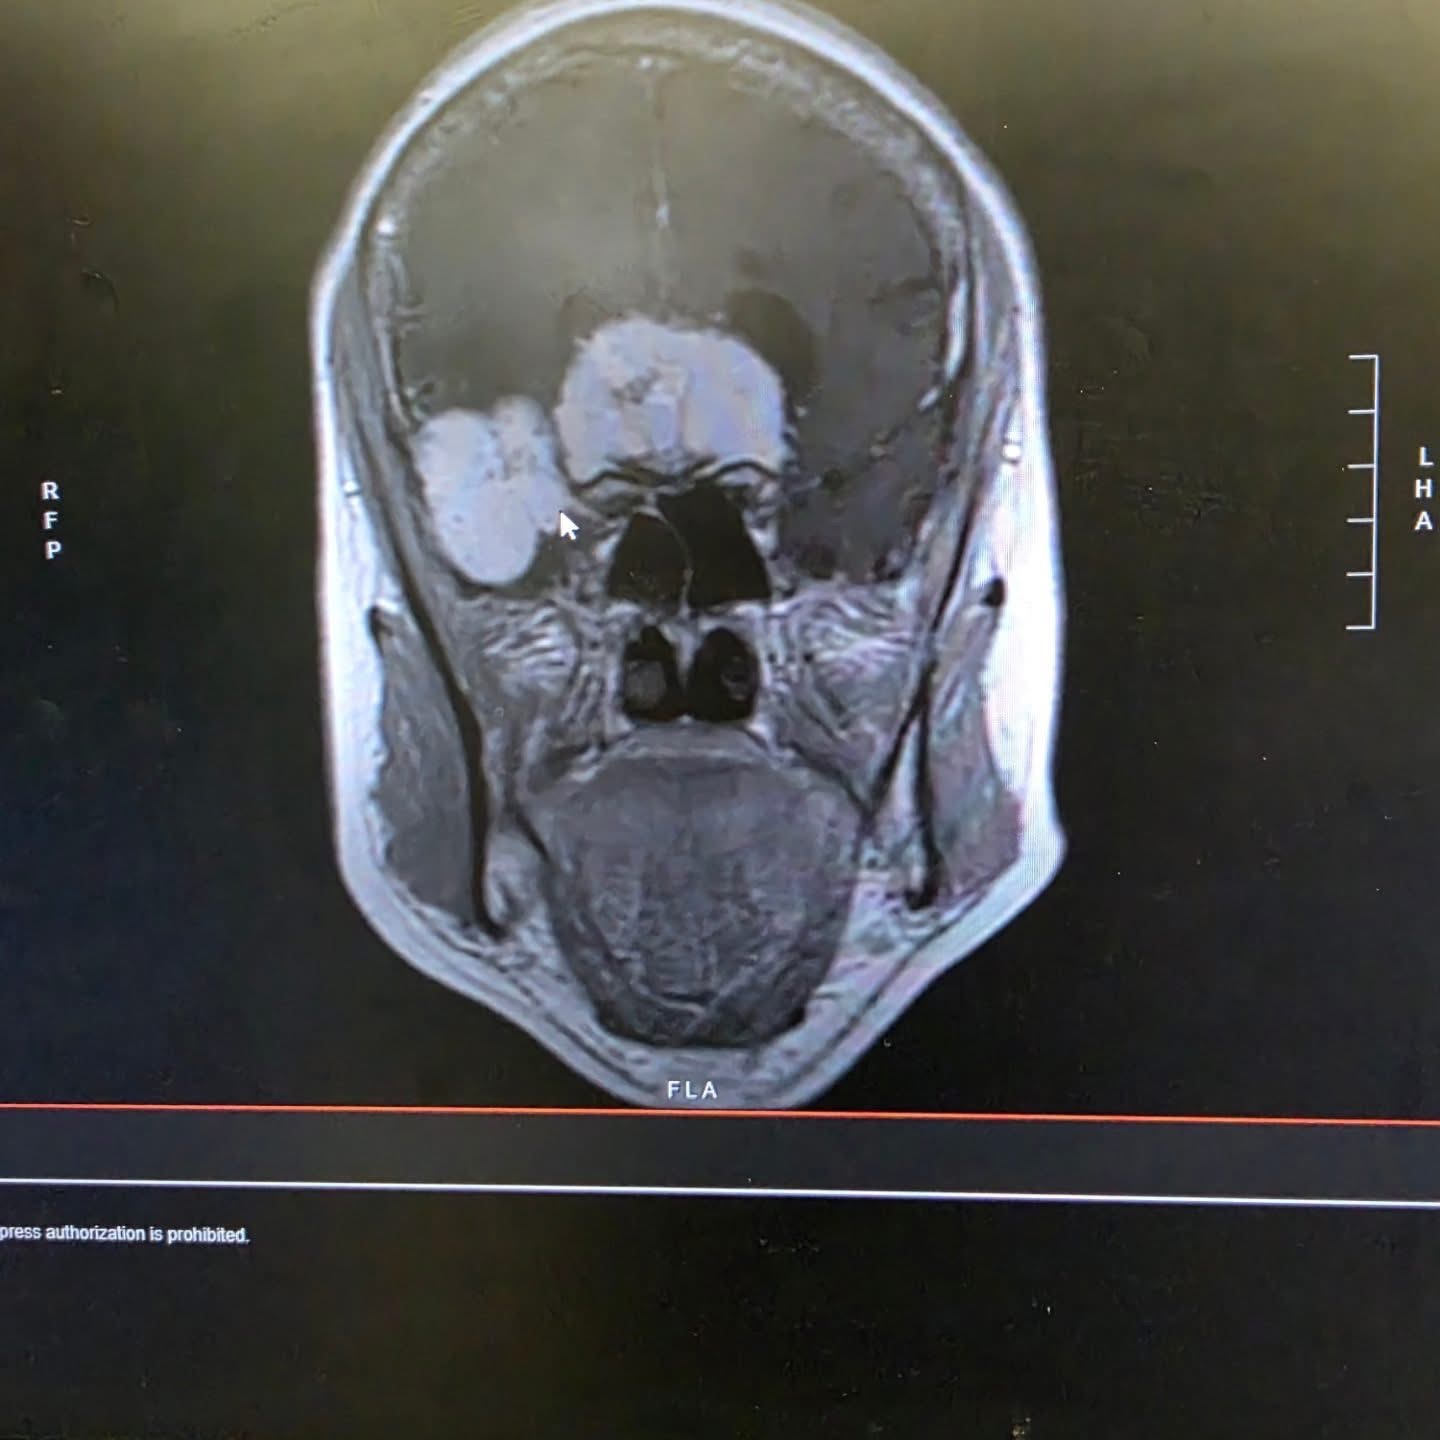

“Long post* I know we've been a little vague with what has been happening with mom, but again lot happened so fast. So with moms permission I am making this post, but she did make it clear, "no pictures" lol but she is allowing me to share her MRI scan. 2nd photo. On Wednesday, June 25th Mom had a scheduled appointment to get a CT scan, because I had expressed my concern of her recent memory loss. It had gotten really bad. I thinking she was experiencing maybe early symptoms of Dementia, was in for an awakening. We were told to check her into the ER right away.(luckily her appointment was at the tulare hospital) still thinking or trying to sike myself into thinking still nothing major, all while anxiety started to kick in, she then got admitted and then off to get an MRI. Now I'll by pass the rest of the behind the scenes. They found two very large masses (tumors) in brain. She was then brought by ambulance to Fresno community where she had a major surgery to remove both masses that Friday June 27th. The Longest 9 hours of our lives!! Its been rough to say the least. Definitely something that wasn't easy to talk about a week ago. She is now on the Physical Therapy floor and doing great. Slow, but great considering the surgery she went through. She is definitely a walking miracle and a big deal on each floor she has been on ( a total of 3) . Im so so thankful for the entire staff here at the Fresno Community Regional Hospital. They have all been amazing not one complaint. Well maybe one, but that's on me lol And a big thank you to my sisters friends! All of you girls!!! I appreciate you girls more than you know!! and everyone else who reached out thank you also!!!! Our hearts our heavy with love and gratitude. From Mom, sister, myself, and our entire family. Thank you!!! ✨️”